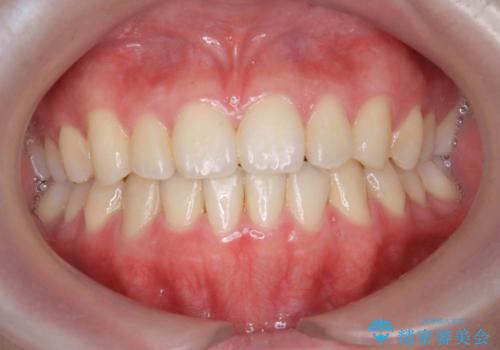

前歯のデコボコをインビザラインでスッキリと仕上げる

マウスピース矯正で前歯のガタつきを改善

上下前歯のデコボコをきれいに インビザラインによる矯正治療